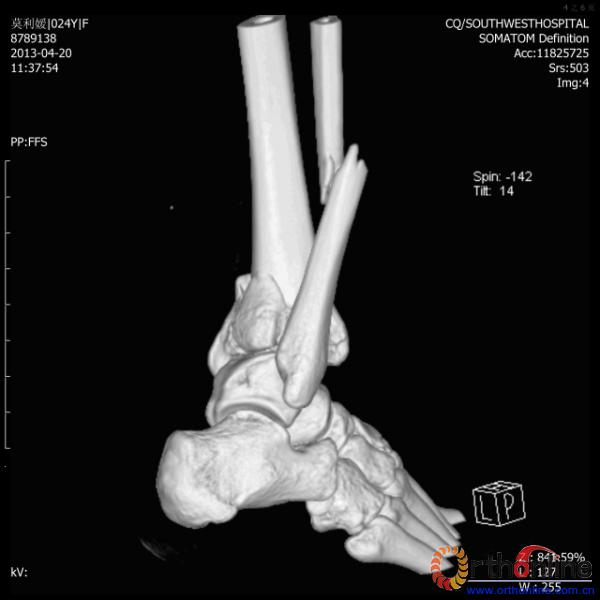

2013年4月20日 8:02分四川雅安芦山县发生7.0级地震后,重庆市有震感,24岁的莫老师在赶往上班的途中突遇此事,导致右踝关节畸形,不能站立和行走。

伤员和家属迅速赶到西南医院,10点关节外科段小军副教授查看伤员后急诊收入院,拍摄X片和急诊行三维CT重建检查,提示踝关节创伤严重,出现三踝骨折伴胫距关节脱位,需要急诊手术治疗。随后段教授与正在四川成都参加“汶川地震5周年灾害医学救治研讨会”的杨柳主任联系,进一步完善救治方案。地震当晚,段教授为该伤员进行急诊手术,手术顺利对复杂骨折进行了解剖复位,有效的钢板螺钉固定。术后伤员的疼痛明显缓解,复查X片,踝关节结构恢复满意。

患者术前CT(一)